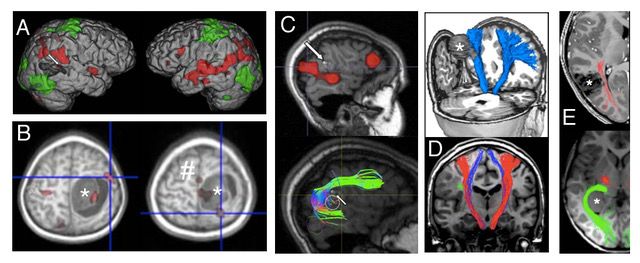

Sorgfältige und individualisierte Planung der Operation auf der Basis hochwertiger MRT Bildgebung, die je nach Lokalisation des Befundes ergänzt werden sollte durch die Darstellung von Motorik und Sprache, Darstellung relevanter Faserbahnsysteme, Charakterisierung des Stoffwechsels, Darstellung von Blutgefäßen und Hirnnerven. Vieles davon können wir dank einer spezialisierten Forschergruppe in Kinderklinik und Neuroradiologie häufig bereits für relativ kleine Kinder realisieren.

Die sogenannte „Zugangsplanung“ sollte die bestmögliche Darstellung des Tumors bei gleichzeitiger Minimierung von Schäden durch den Weg zum Tumor ermöglichen.

Die Operationsstrategie, die sich aus dieser detaillierten Planung ergibt, hat einen erheblichen Anteil am operativen Erfolg.